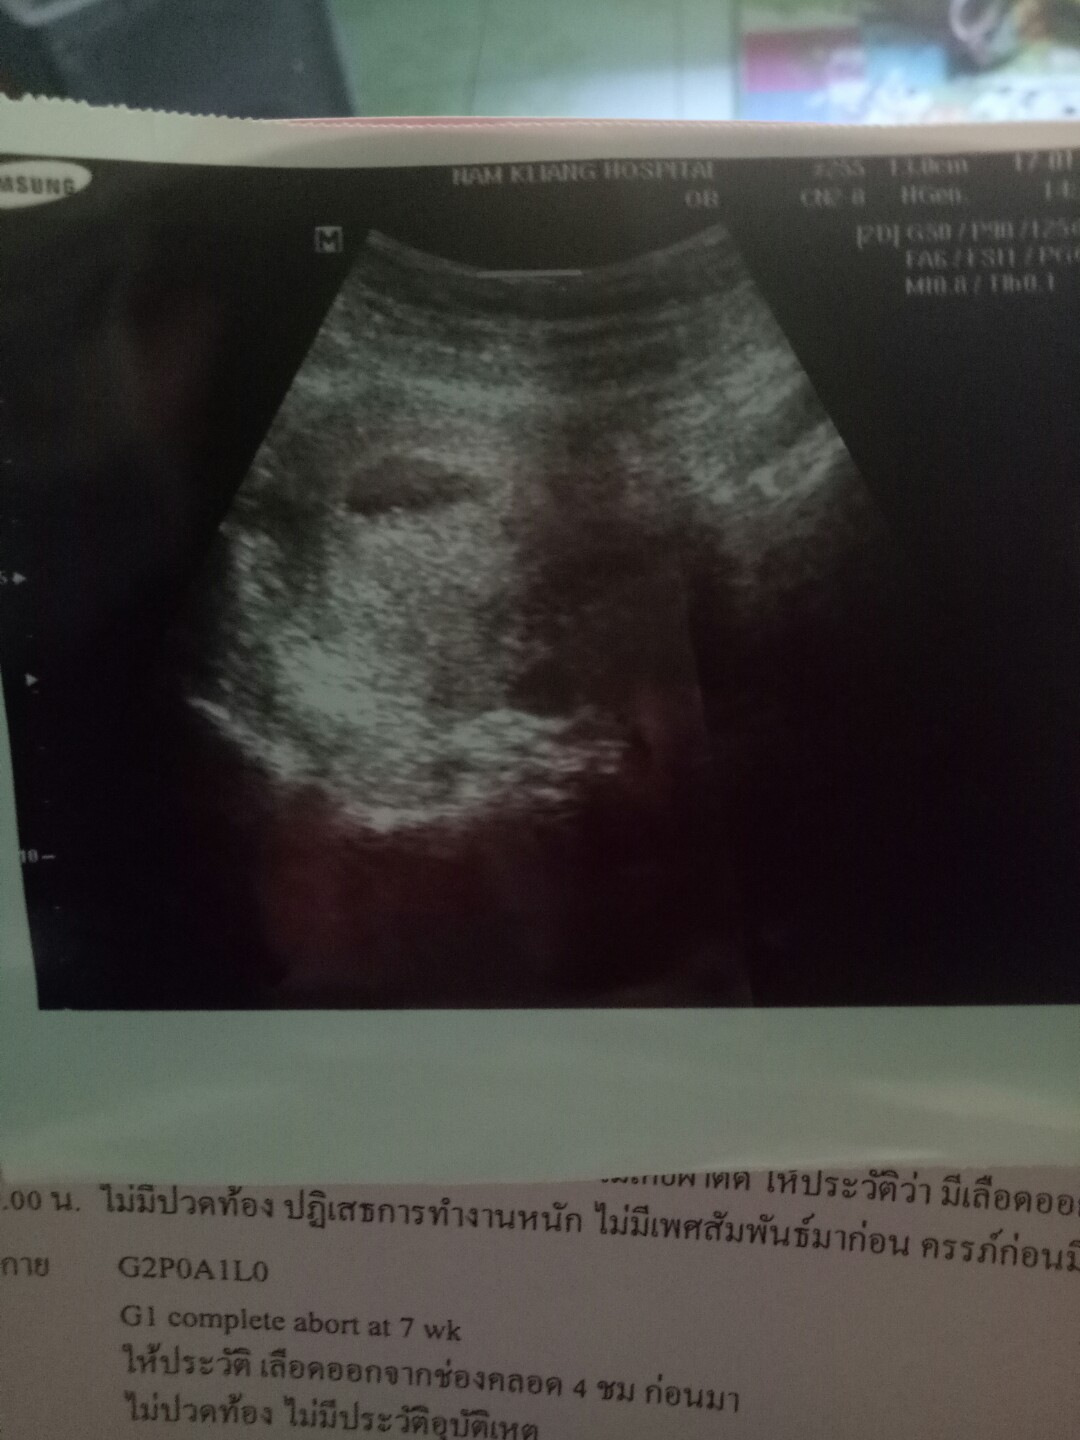

9w+6dซาววันนี้ค่าาา ทีมสิงหา

15 สิงหา 2020 ค่า 9สัปดาห์6วัน 🥰